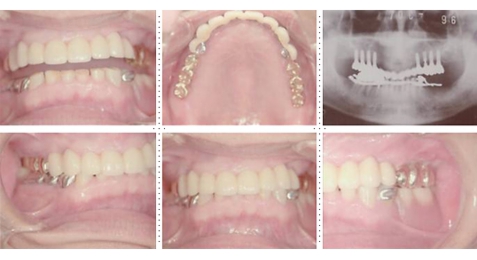

症例3

73才 男性

上顎2本、下顎1本だけ歯が残り、入れ歯を使っておりますが、痛みがありよく噛めない状態。

上顎1本の歯だけを残し、インプラント8本埋入。下顎は歯を抜き、インプラント7本埋入。上下顎とも、セラミック(MB)クラウンをセット。仕事・生活ともに活力が出て、新しい人生が始まったようであると喜んでいただきました。